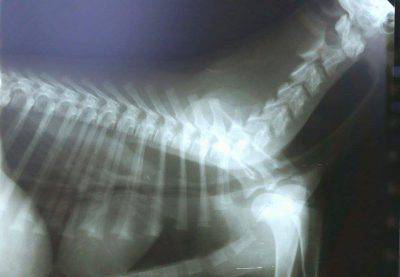

En los cachorros jóvenes, los cuerpos extraños pueden atascarse en la boca, la faringe o el esófago y causar hipersalivación y dificultad para tragar. Para identificar la causa, el cachorro debe ser sometido a sedación y anestesia. También se requerirá una radiografía.

El diagnóstico definitivo se realiza mediante fluoroscopia., que es una imagen radiográfica en movimiento que monitorea el tránsito de alimentos recubiertos con bario (medio de contraste) una vez ingeridos.